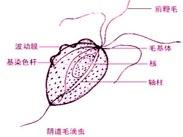

滴蟲性陰道炎

628健康網為您分享有關滴蟲性陰道炎的癥狀,滴蟲性陰道炎的治療方法,滴蟲性陰道炎的預防知識,滴蟲性陰道炎的癥狀圖片,滴...